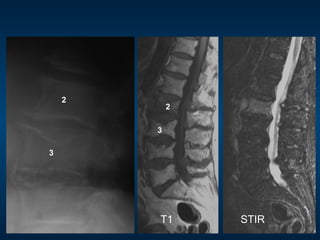

MRI: pre-vertebroplasty

STIR

2

3

T1 STIR

•  85 year old female

•  Severe acute on chronic mechanical

back pain

– Can’t sleep

– Limited walking to only a few steps

•  Spontaneous onset

•  No known trauma